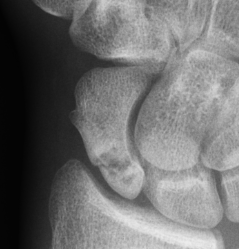

Nonunion with minimal displacement and minimal resorption

Nonunion with significant displacement and bone resorption

Proximal pole fracture with displacement and absorption